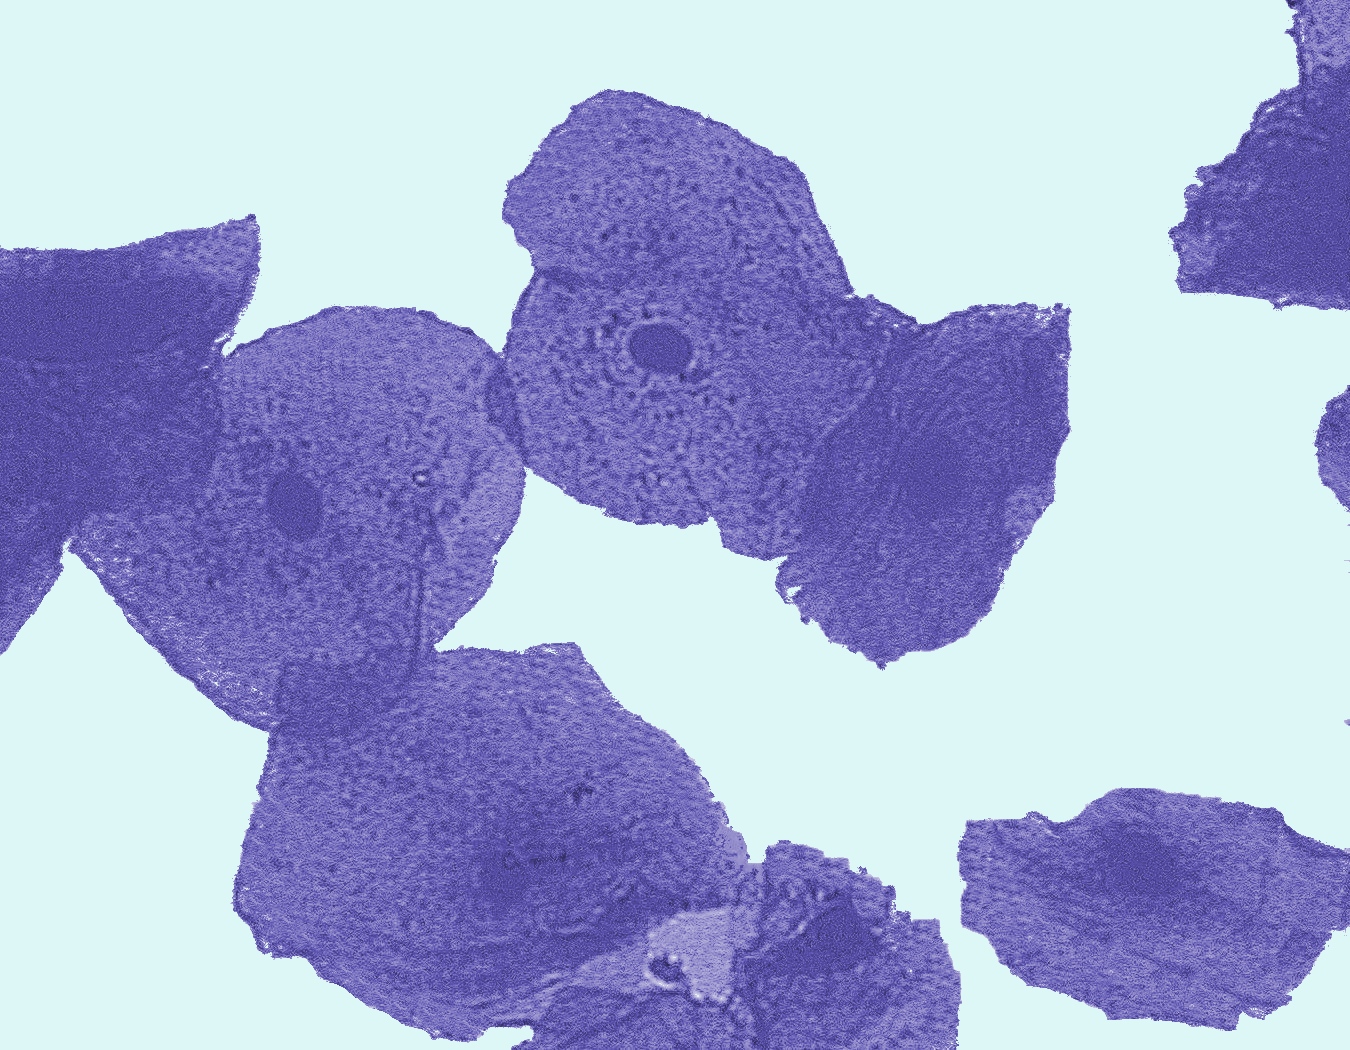

Biology Graphics (14-16)

Select the images you want and just save!

Thousands of images all created especially for education.